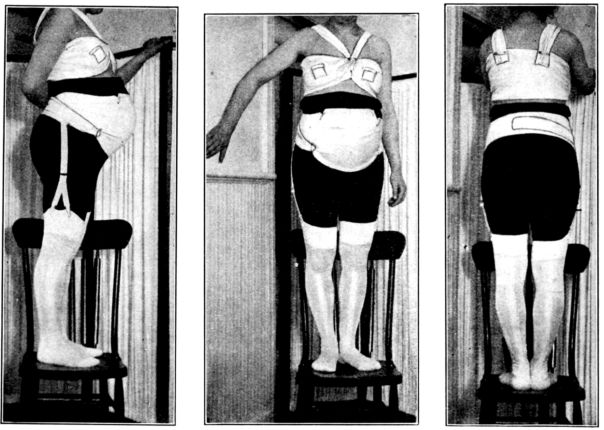

| 34. | Front view of home-made abdominal binder | 123 |

| 35. | Side view of same | 123 |

| 36. | Back view of same | 123 |

| 37. | Abdominal binder used in above | 124 |

| 38. | Front view of home-made stocking supporters | 124 |

| 39. | Back view of same | 124 |